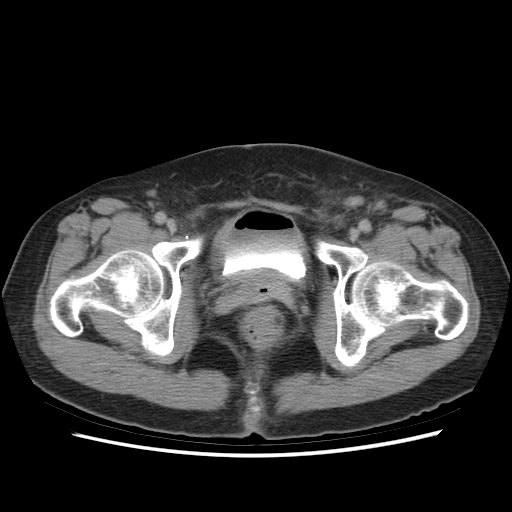

One hundred consecutive IC patients were investigated by symptom score, urodynamic study, cystoscopic hydrodistention, and bladder CT study. The BWT is divided into smooth (n=49), focal thickness (n=15), and diffuse thickness (n=36) subtypes, which are demonstrated in Figure 1.

Figure 1. Subtypes of BWT demostrated on CT